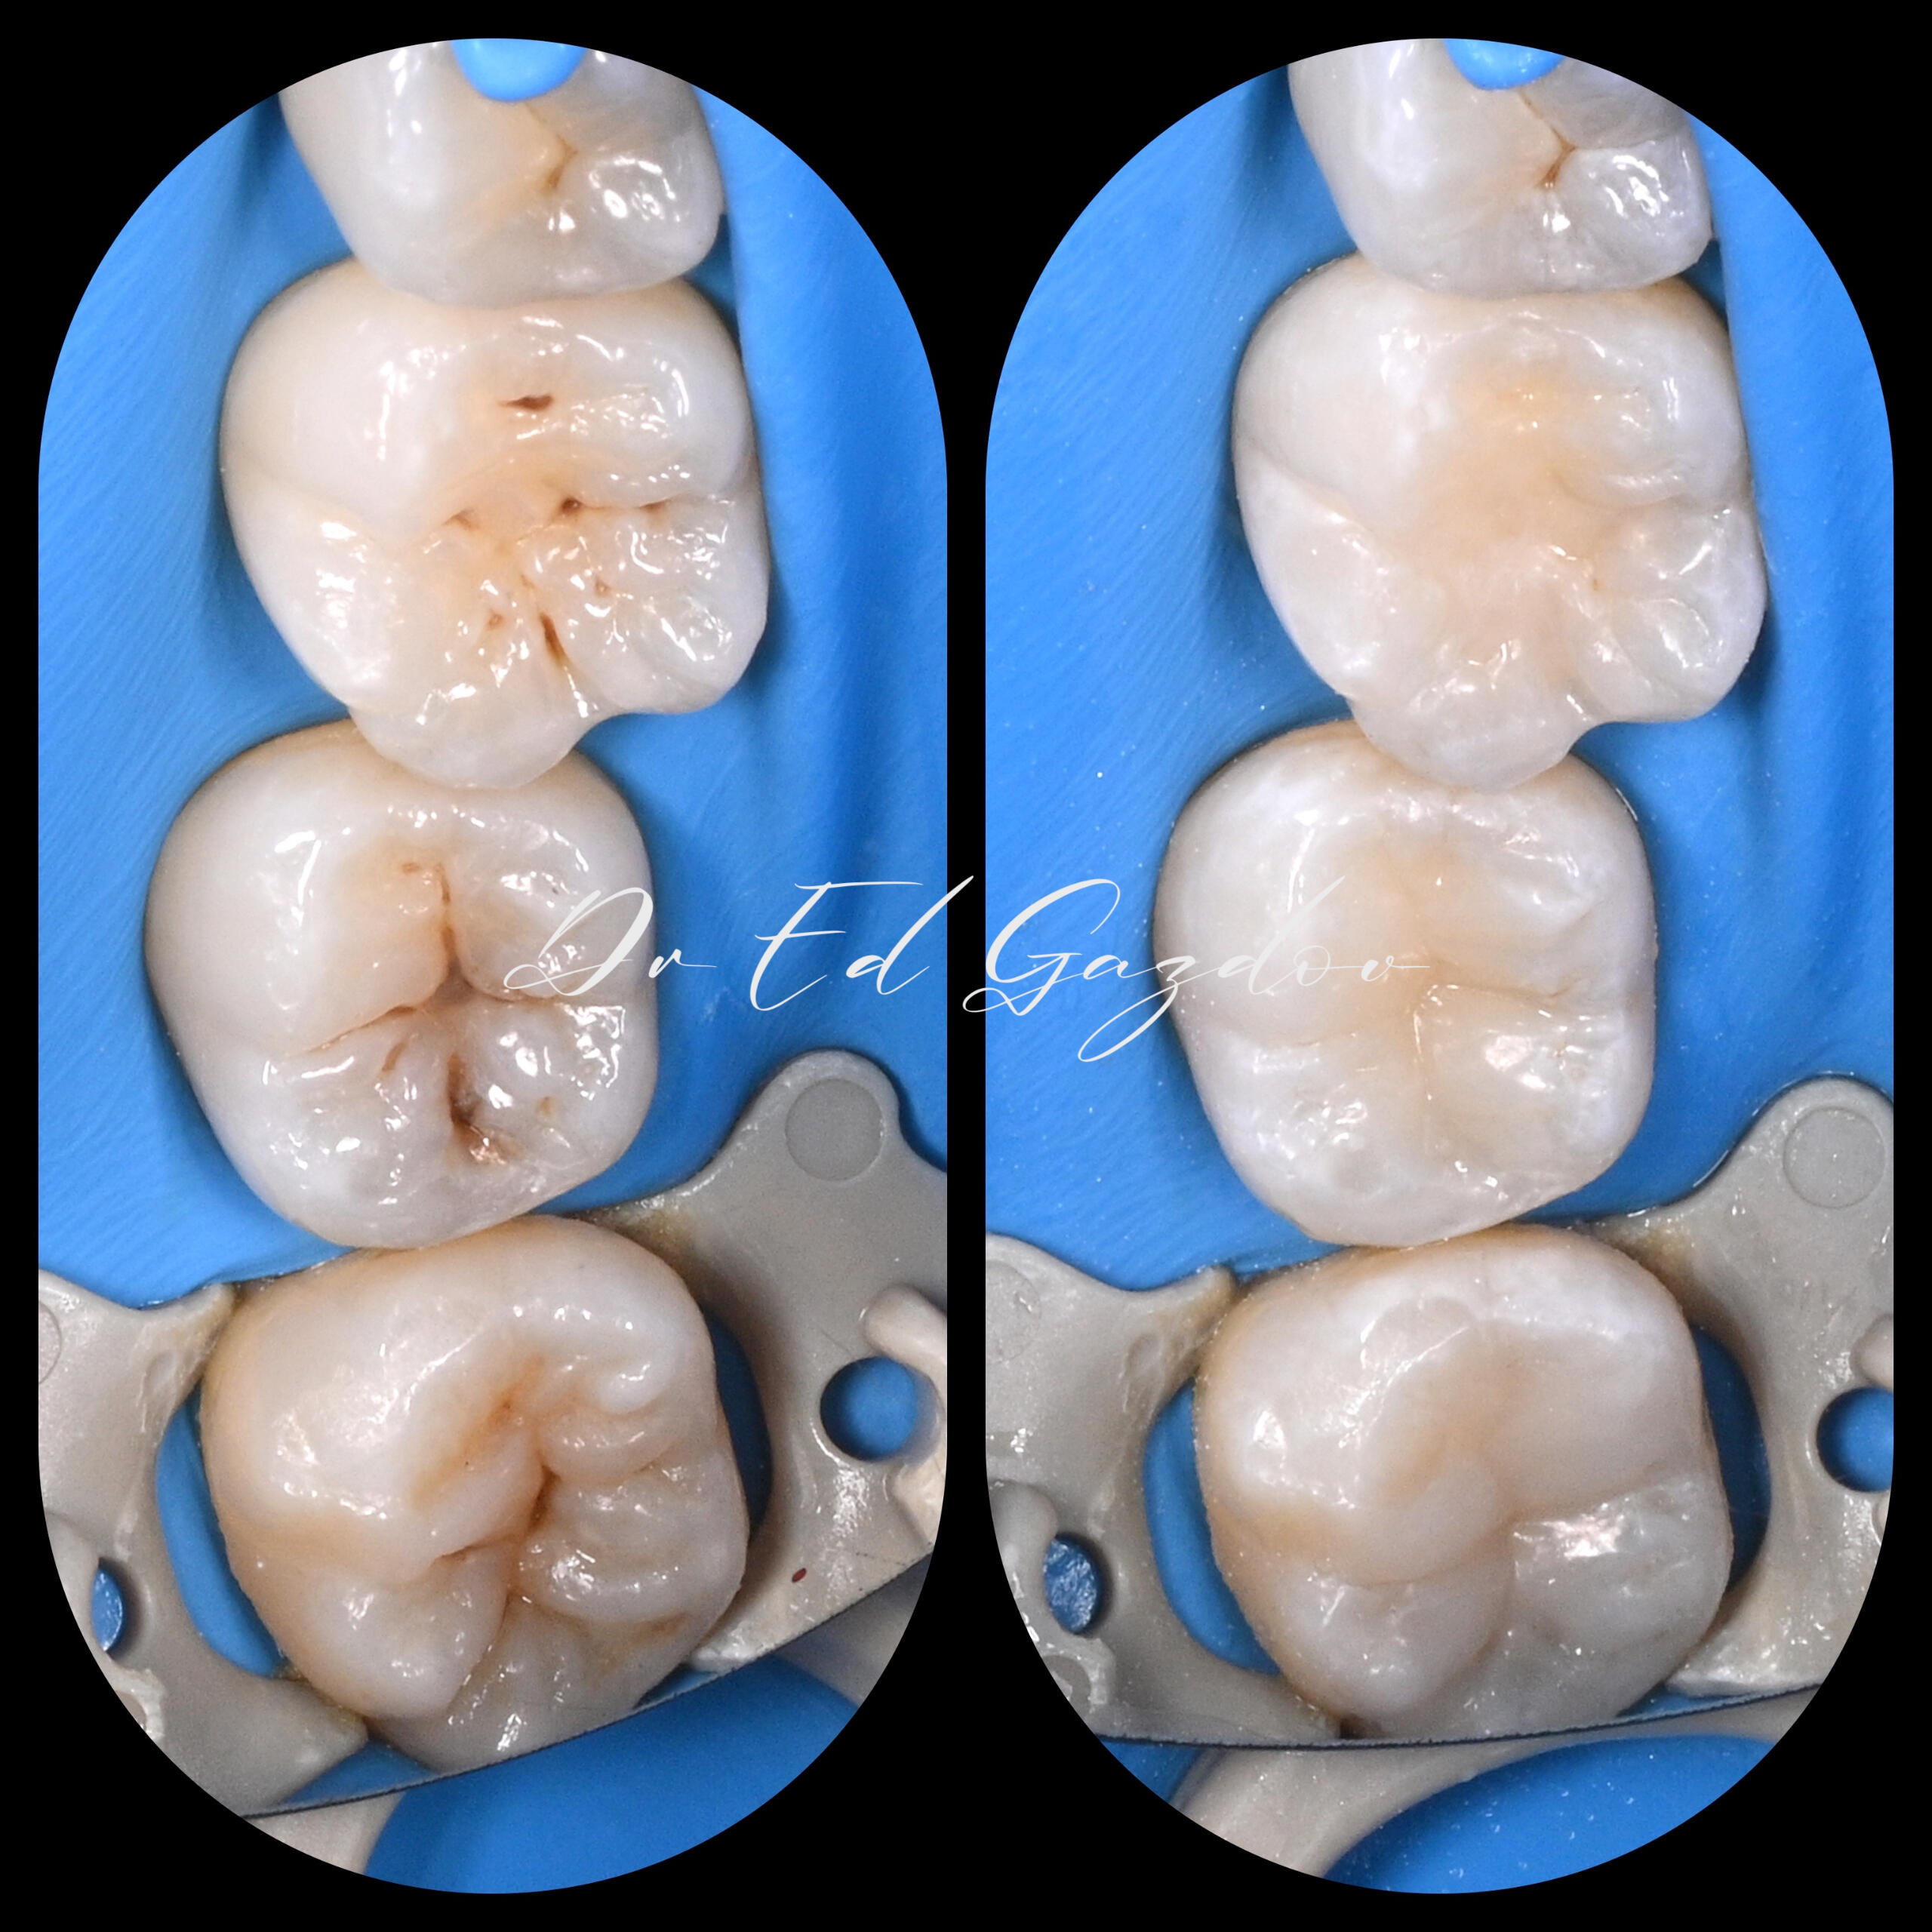

BEFORE AND AFTER

Real Results. Real Patients.Every image you see here shows real treatments carried out personally by Dr. Eduard Gazdov — from start to finish.We treat complex cases using modern, evidence-based protocols. Whether it’s a full smile makeover, single-tooth restoration, or managing difficult retreatments, our approach is built on precision, communication, and care.🦷 We offer:

• Direct composite restorations and bonding for small chips or cosmetic reshaping

• CEREC crowns and inlays designed and delivered chairside

We work with magnification, rubber dam isolation, high-end materials and lab support, and always explain every step along the way.